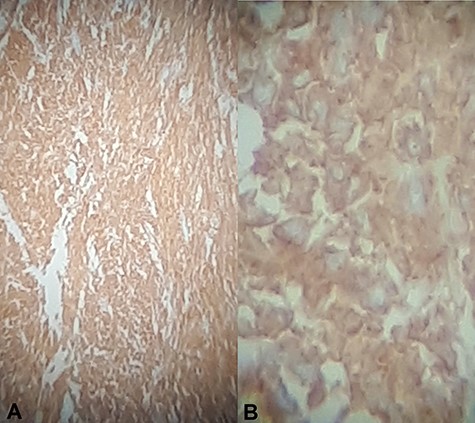

Immunohistochemical staining for CD 117 was positive confirming the diagnosis of a GIST (Fig. 6). Molecular assessment for c-KIT D816V and PDGFRA D842V mutations (markers of resistance to adjuvant imatinib therapy) were performed and were negative. Thus adjuvant imatinib 400 mg/day was commenced.

Immunohistochemical staining for CD117 (A) Jejunal mass at ×4 magnification, (B) jejunal mass at ×40 magnification is diffusely positive.